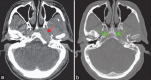

Skull base osteomyelitis (SBO) is a complex and fatal clinical entity that is often misdiagnosed for malignancy. SBO is commonly a direct complication of otogenic, sinogenic, odontogenic, and rhinogenic infections and can present as central, atypical, or pediatric clival SBO. This review describes the clinical profile, investigational approach, and management techniques for these variants. A comprehensive literature review was performed in PubMed, MEDLINE, Research Gate, EMBASE, Wiley Online Library, and various Neurosurgical and Neurology journals with the keywords including: SBO, central or atypical SBO, fungal osteomyelitis, malignant otitis externa, temporal bone osteomyelitis, and clival osteomyelitis. Each manuscript's reference list was reviewed for potentially relevant articles. The search yielded a total of 153 articles. It was found that with early and aggressive culture guided long-term intravenous broad-spectrum antibiotic therapy decreases post-infection complications. In cases of widespread soft tissue involvement, an early aggressive surgical removal of infectious sequestra with preferentially Hyperbaric Oxygen (HBO) therapy is associated with better prognosis of disease, less neurologic sequelae and mortality rate. Complete resolution of the SBO cases may take several months. Since early treatment can improve mortality rates, it is paramount that the reporting radiologists and treating clinicians are aware of the cardinal diagnostic signs to improve clinical outcomes of the disease. It will decrease delayed diagnosis and under treatment of the condition. However, due to rarity of the condition, complete prognostic factors have not fully been analyzed and discussed in the literature.